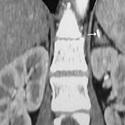

Thrombose de la veine porte révélant un syndrome de Cushing du sujet âgé

Wafa Chebbi, Olfa Berriche

PAMJ. 2014; 18: 186. Published 04 July 2014